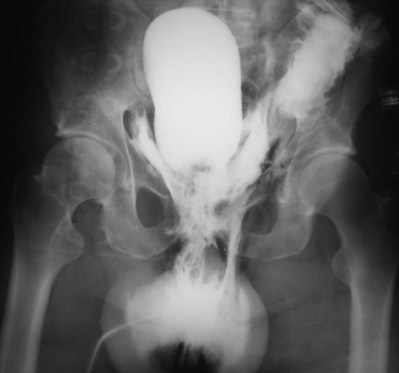

A dense, flame-shaped collection of contrast material in the pelvis is characteristic of extraperitoneal extravasation (Fig. 88–9). Depending on fascial integrity, contrast material may extend beyond the confines of the pelvis and be visualized in the retroperitoneum, scrotum, phallus, thigh, and/or abdominal wall. The amount of extravasation is not always proportional to the extent of bladder injury. Intraperitoneal extravasation is identified when contrast material outlines loops of bowel and/or the lower lateral portion of the peritoneal cavity.

Figure 88–9 Plain film cystogram reveals extraperitoneal bladder rupture with extravasation into scrotum. Surgical exploration revealed anterior bladder neck and prostatic urethral laceration.